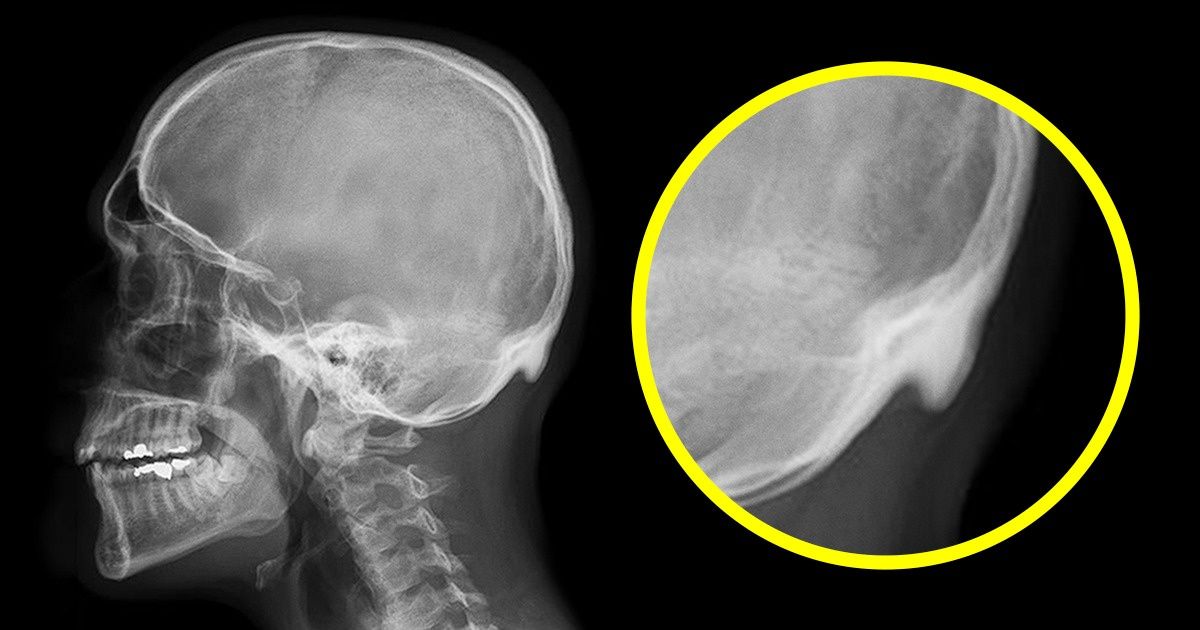

Durante a pesquisa, foram entrevistadas 218 pessoas entre 18 a 30 anos. O Dr. David Shahar encontrou uma projeção óssea na nuca de 41% dos participantes. Essa projeção é considerada anormal partir de 10 mm. E o comprimento da projeção que apareceu em 10% dos entrevistados, era de mais de 20 mm; o comprimento máximo nos homens era de 35,7 mm, e o nas mulheres de 25,5 mm.

Na segunda pesquisa que foi realizada, participaram 1.200 pessoas entre 18 a 86 anos. De acordo com os resultados, a projeção foi encontrada na nuca dos mais jovens. Esse foi o motivo que levou Dr. Shahar e seu colega Mark Sayers a assumirem que esse trauma ósseo é causado pela postura inadequada. A cabeça fica inclinada de maneira errada, e os locais de junção dos músculos com o crânio ficam sob pressão. Dessa forma, acontecem as anomalias nos ossos e no tendão. Segundo os cientistas, a projeção não é perigosa, porém o problema principal seria a coluna curvada, o que leva a outros problemas de saúde.

O Dr. Shahar afirma ainda que o comprimento da projeção continuará aumentando a cada geração. Porém, alguns cientistas discordam dessa afirmação dos pesquisadores e não acreditam nos resultados dessa pesquisa. Apenas com o passar dos anos nós conseguiremos descobrir quem está certo sobre tal assunto.